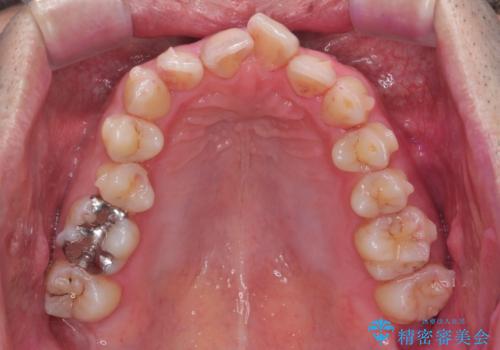

- 前歯の並びを気にして来院。

右の歯並びが1本分上が前にずれていました。

本来は抜歯して上の前歯を引っ込めるか、歯を一本分上の奥歯を後ろに下げるやり方が正攻法ですが、

奥歯のかみ合わせを特に変えず、前歯の並びを整える治療をおこないました。

奥歯のかみ合わせは1本分ずれているとはいえ、1歯対2歯の交互のかみ合わせになっているため、そのままにしてもそこまで大きなデメリットはありません。